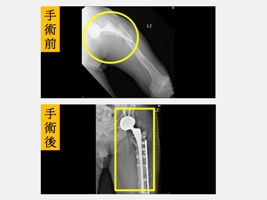

台中市大里區一名82歲劉姓男子有高血糖、高血壓和高血脂等病史,兩側髖關節曾經接受過人工關節置換手術。今年中秋節連假與家人賞月烤肉同樂時不小心滑了一跤後跌坐在地上,左腳痛到無法動彈,家人趕緊將劉先生送到仁愛長庚合作聯盟醫院(大里仁愛醫院)急診室,經檢查後才發現是人工髖關節旁的股骨粉碎性骨折,而且原本的人工關節也整個鬆動了。經骨科部黃贊文部長啟動「宜樂適快速康復手術療程(ERAS)」後,安排骨質疏鬆藥物治療,並配合健保署的「手術後疼痛中醫輔助療法」,在中西醫合併治療下,劉先生已順利出院。只是一個單純的滑倒卻造成如此嚴重的後果,劉先生現在回想起來,仍是心有餘悸。